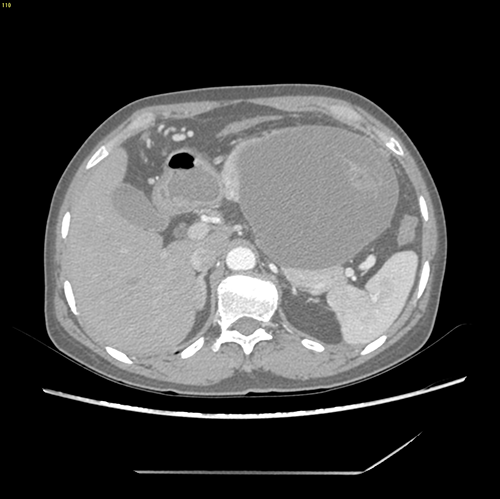

胰体尾囊腺瘤---腹腔镜胰体尾切除